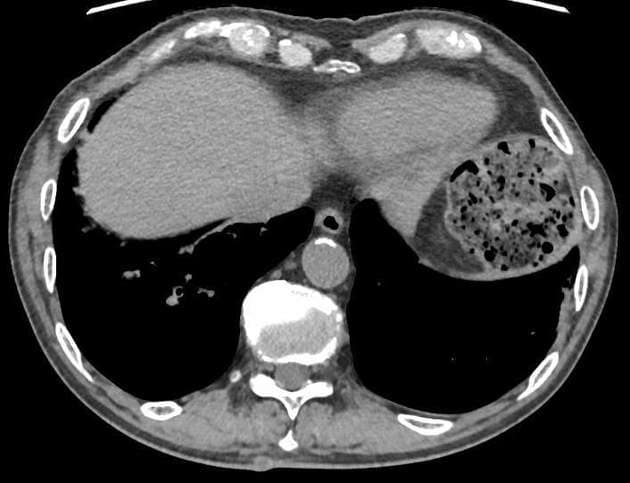

CT

CT là phương tiện hình ảnh chính ("workhorse") để đánh giá tụy:

hình ảnh ung thư biểu mô tuyến ống

các khối không giới hạn rõ với phản ứng xơ hóa rộng rãi xung quanh

thường giảm tỷ trọng trên pha động mạch ở 75-90% trường hợp, có thể đồng tỷ trọng trên các pha trễ (do đó cần chụp nhiều thì khi nghi ngờ ung thư tụy)

có thể thấy dấu hiệu hai ống

vôi hóa hiếm gặp và khi có, thường thứ phát do các bệnh lý nền (ví dụ: viêm tụy mạn tính)

tỷ lệ đường kính ống tụy mở rộng so với chiều rộng trước – sau của tuyến tụy khoảng 0,5 có thể xuất hiện, phản ánh sự giãn ống và teo nhu mô